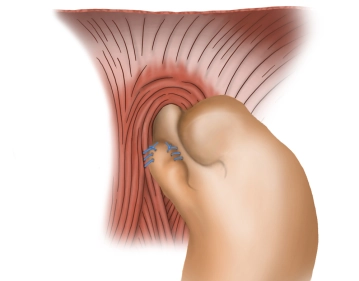

Fixation der Fundusmanschette I

![Fixation der Fundusmanschette I]()

Toneinstellungen Der vordere Vagusast wird eindeutig identifiziert. Unter Schonung des selben wird zunächst das rechte Fundusohr fortlaufend an die rechte Seite des Ösophagus fixiert (geflochtener, nicht resorbierbarer Faden Stärke 2-0). Zusätzlich erfolgt dann die Fixation des nach rechts gezogenen Fundusanteils mit einer weiteren fortlaufenden Naht (geflochtener, nicht resorbierbarer Faden Stärke 2-0) an den rechten Zwerchfellschenkel.